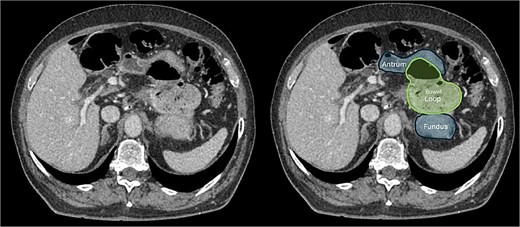

A contrast-enhanced computed tomography (CT) scan of the abdomen and pelvis initially suggested small bowel telescoping in the left upper quadrant above the duodenum, with superior displacement of the stomach (Fig. 1). These findings were most consistent with an internal hernia. Additionally, fecalized contents within the herniated bowel suggested delayed transit, likely indicating a partial obstruction.

CT scan of the abdomen showing that the colon passing above and to the left of the lesser curvature of the stomach, implying that it had herniated through the foramen of Winslow and into the lesser sac.